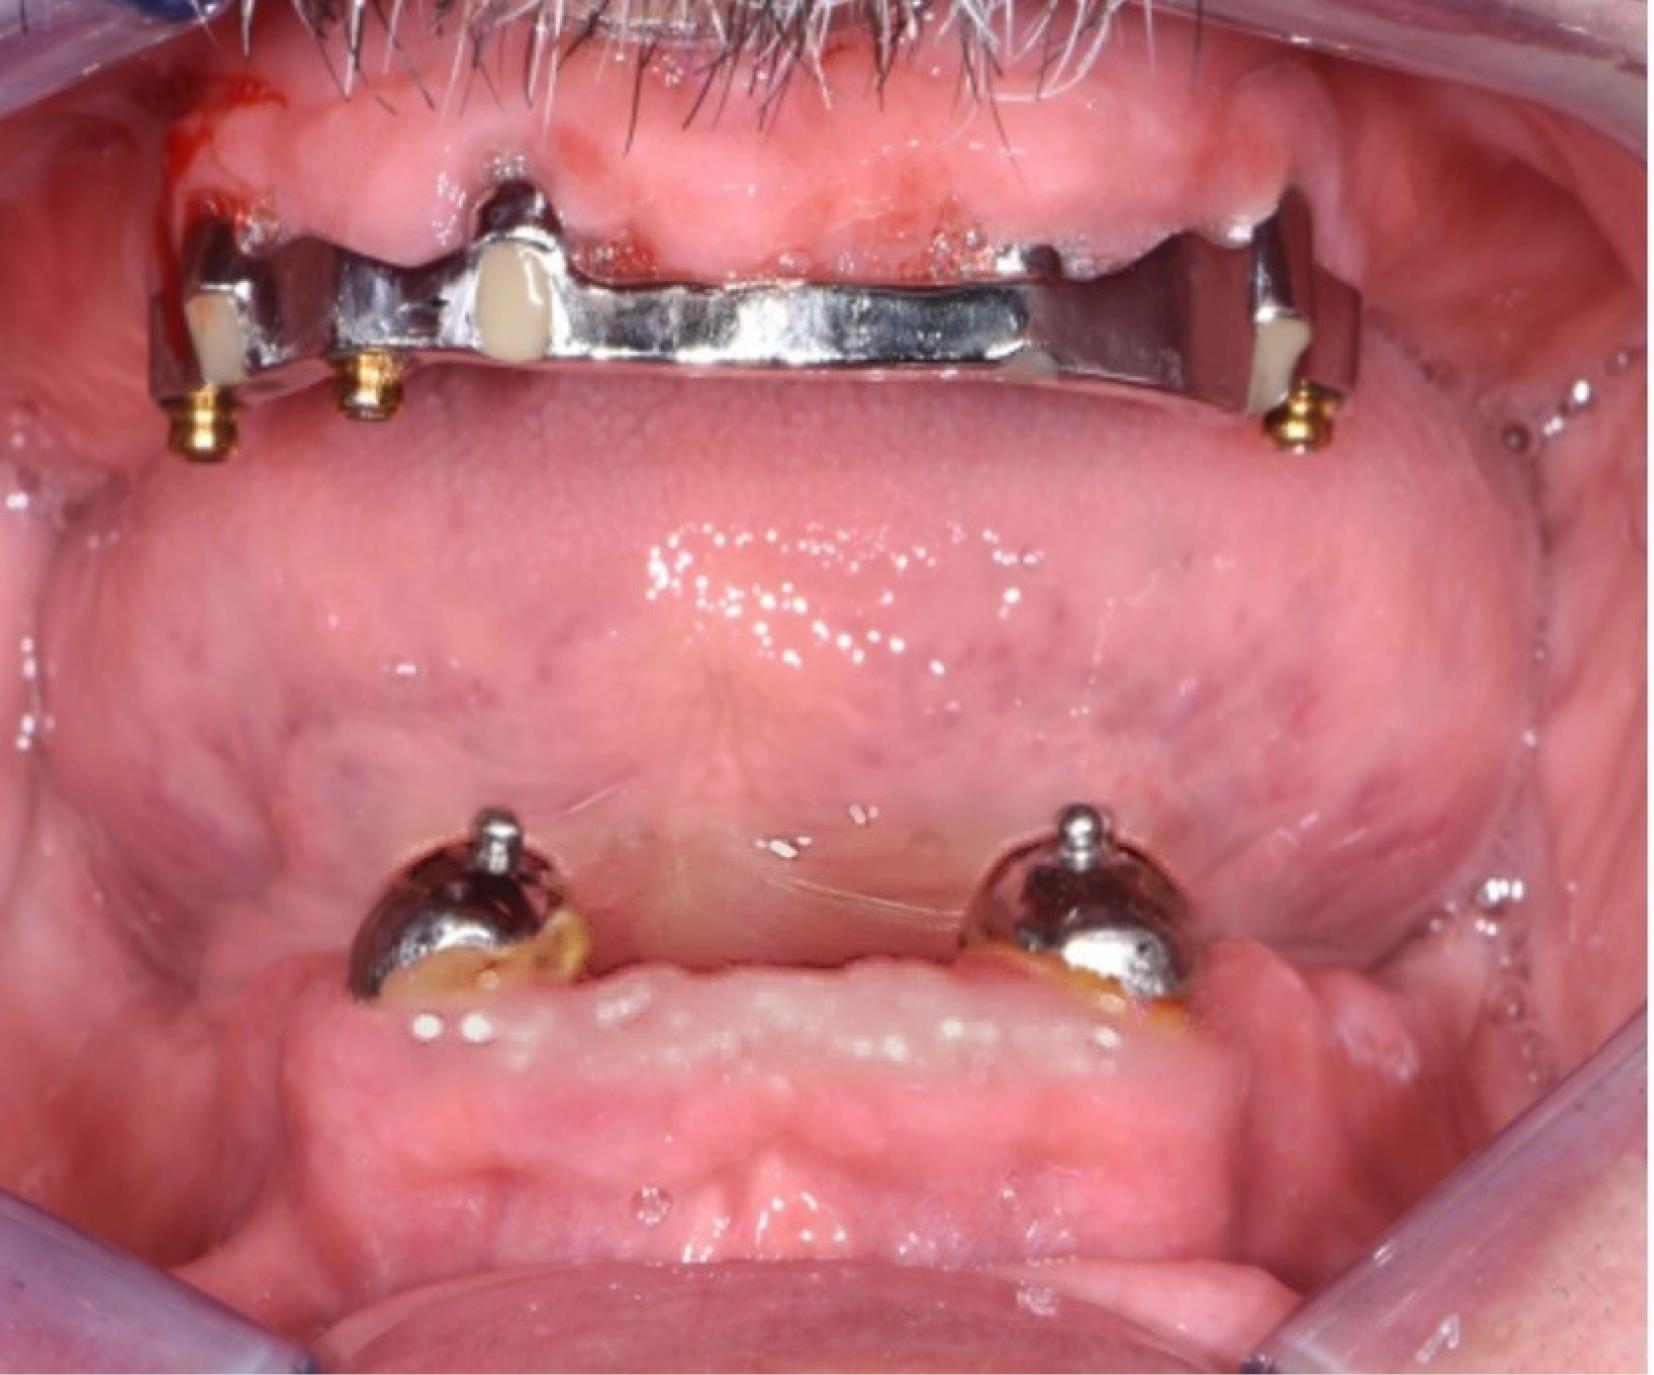

The present case report follows the CARE checklist (https://www.care-statement.org/checklist). A 60-year-old partially edentulous male patient, complaining of functional and aesthetic discomfort, visited our dental clinic. The patient wore an implant-supported bar-engaged removable denture in the upper jaw. At the same time, the mandible was rehabilitated with an overdenture retained by two ball attachments on the residual cuspid roots (Figure 2). A clinical intraoral examination showed an improvable occlusal relationship between the arches, with poor lower denture stability. The patient requested to be treated as quickly as possible and was willing to wear a fixed mandibular prosthesis immediately. After taking a panoramic x-ray, the occlusion was balanced, and a correct vertical dimension was achieved between the jaws by adjusting the overdentures. The inferior prosthesis was scanned, and the standard tessellation (STL) data were imported to the dedicated software. A cone-beam CT of the jaws was taken, and the relative DICOM files were digitally acquired and matched with the STL ones. The residual mandibular alveolar process appeared dramatically reduced in the horizontal dimension, with about a 5-mm thickness in the frontal and posterior zones (Figure 3). The option of the mini-implant was proposed to the patient since he firmly kept his decision to undergo one-session treatment despite being clearly warned about the unknown predictability of such an approach.

Figure 2.

Starting clinical situation after the removal of the superstructure